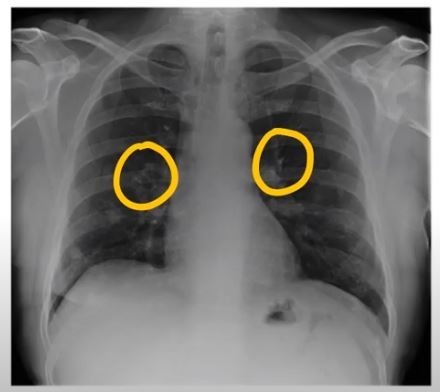

안녕하세요! 오늘은 폐렴의 초기 증상에 대해 알아보려고 합니다. 갑자기 기침이 심해지거나 숨이 차는 등 평소와 다른 호흡의 변화가 있을 때, 그 증상이 단순한 감기인지 아니면 폐렴으로 이어지는 문제인지를 구분하는 것이 중요합니다. 폐렴은 빠르게 진행될 수 있기 때문에, 초기 증상에 대한 인식을 높이는 것이 예방과 치료에 큰 도움이 됩니다.

폐렴 초기증상 폐렴 초기증상